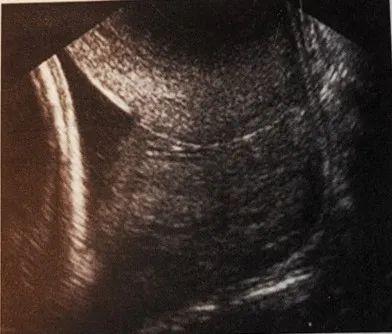

什么是宫颈机能不全?如何诊治?宫颈机能不全临床上主要依据病史、超声检查和典型临床表现进行诊断。1、病史最常见的病史是指孕晚期出现无痛性流产或极早产史;既往有宫颈手术创伤病史,如宫腔镜下子宫纵隔切除术、宫颈锥切术、流产术或引产术等反复机械性扩张宫颈等。2、超声检查超声检查包括经腹、经会阴和经阴道3种方式,指南推荐经阴道超声测量宫颈,也是目前公认的诊断方法,能有效地评估宫颈缩短情况。妊娠24周前宫颈长度≤25 mm,伴有进行性宫颈扩张。非妊娠时,阴道超声测量宫颈长度≤25 mm或8号宫颈扩张棒无阻力地通过宫颈内口。什么是宫颈机能不全?如何诊治?正常闭合宫颈管 什么是宫颈机能不全?如何诊治? 扩张型宫颈管 什么是宫颈机能不全?如何诊治?超声测量宫颈示意图